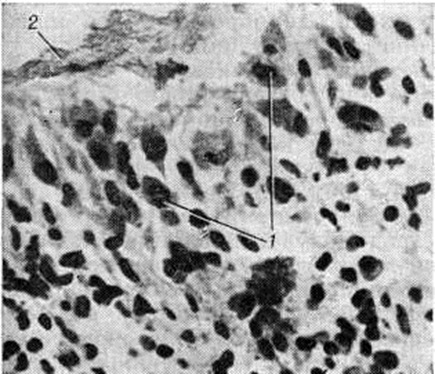

В суставах при развёрнутой клинические, картине заболевания обнаруживается ворсинчатое разрастание синовиальной оболочки (рисунок 1), в части случаев наползающей в виде паннуса на поверхность суставного хряща. При этом в суставном хряще определяются эрозии, трещины, щели; его остатки сухие и зернистые на вид. В суставных полостях обнаруживается увеличенное количество вязкой мутной синовиальной жидкости, постоянно отмечается утолщение и склероз суставной капсулы, имеются фиброзные спайки. Полная облитерация суставной полости спайками ведёт к развитию фиброзного анкилоза (смотри полный свод знаний). Пролиферация остеоидной ткани сопровождается развитием остеофитов (смотри полный свод знаний) и костных анкилозов.

В гистологический картине синовита выделяют следующие изменения: 1) поражение сосудов микроциркуляторного русла; 2) гиперплазию и гипертрофию синовиальных клеток; 3) воспалительную клеточную инфильтрацию; 4) разрастание грануляционной ткани, склероз, липоматоз синовиальной собственной пластинки. Повышается проницаемость стенок сосудов микроциркуляторного русла, сопровождающаяся выходом фибринозного экссудата и образованием очагов фибриноида в синовиальной собственной пластинке и фибриноподобных наложений на поверхности синовиальной оболочки. Иммуноморфологически в очагах фибриноида и в фибриноподобных наложениях выявляются фибрин, иммуноглобулины (G, А, М) и С3-фракция комплемента. При обострении воспаления постоянно отмечается продуктивный или продуктивно-деструктивный васкулит с фиксацией в сосудистой стенке иммуноглобулинов и комплемента. В глубоких слоях синовиальной оболочки (смотри полный свод знаний) изредка определяются ревматоидные узелки — небольшие участки фибриноидного некроза, окружённые макрофагами и лимфоцитами. В 80% случаев встречается гиперплазия и гипертрофия синовиоцитов с характерным палисадообразным их расположением (рисунок 2). С помощью электронно-микроскопического исследования обнаружено, что гипертрофия синовиоцитов происходит за счёт гиперплазии их органелл, особенно зернистой эндоплазматической сети, полисом, аппарата Гольджи и лизосом (рисунок 3). В гиперплазии ворсинчатого слоя синовиальной оболочки участвуют синовиоциты всех трёх типов (А, В и С). На ранних стадиях обострения воспаления клеточная инфильтрация в синовиальной оболочке скудная, представлена лимфоцитами, макрофагами и полиморфно-ядерными лейкоцитами. В дальнейшем отмечается лимфоидно-плазмоцитарная инфильтрация (рисунок 4), иногда с формированием лимфоидных фолликулов. Параллельно при иммунофлюоресцентном изучении Т и В-лимфоцитов синовиальной оболочки при Ревматоидный артрит Банкхерст (A. D. Bankhurst) с соавторами (1976) выявил преобладание Т-лимфоцитов. В синовиальной оболочке отмечается значительная пролиферация фибробластов. В синовиальной собственной пластинке и фиброзном слое наблюдается разрастание грануляционной ткани с исходом в склероз (смотри полный свод знаний) и липоматоз (смотри полный свод знаний).